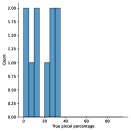

A few sample images and the corresponding masks of the polyp dataset in HyperKvasir are shown in Fig 2. The polyp images are RGB images. The masks of the polyp images are single-channel images with white () for true pixels, which represent polyp regions, and black () for false pixels, which represent clean colon or background regions. In this dataset, there are different sizes of polyps. The distribution of polyp sizes as a percentage of the full image size is presented in the histogram plot in Fig 3, and we can observe that there are more relatively small polyps compared to larger polyps. Additionally, a subset of this dataset was used to prove that the performance of segmentation models trained with small datasets can be improved using our SinGAN-Seg pipeline, and the whole dataset was used to show the effect of using SinGAN-Seg generated synthetic images instead of a large dataset which has enough data to train segmentation models. In this regard, this dataset was used for two purposes:

To understand the difference between the mask distribution of real images and synthetic images, we plotted pixel distribution of masks of synthetic images in Fig 6. This plot is comparable to the pixel distribution presented in Fig 3. The randomness of the generations made differences in the distribution of true pixel percentages compared to the true pixel distribution of real masks of real images. However, the overall shape of synthetic data mask distribution shows a more or less similar distribution pattern to the real true pixel percentage distribution.